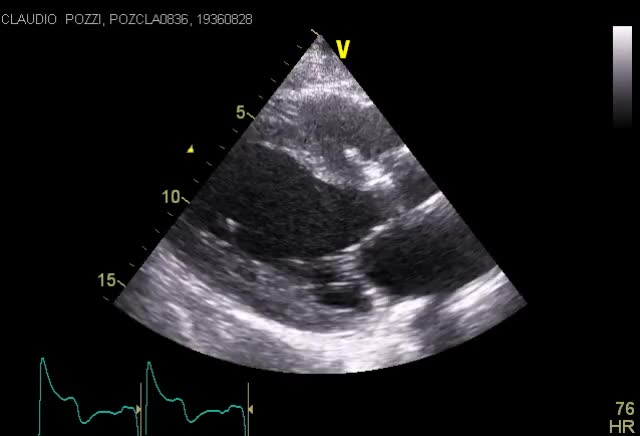

Titolo:

Cardiomiopatia restrittiva

Autore:

Andrea Barbieri